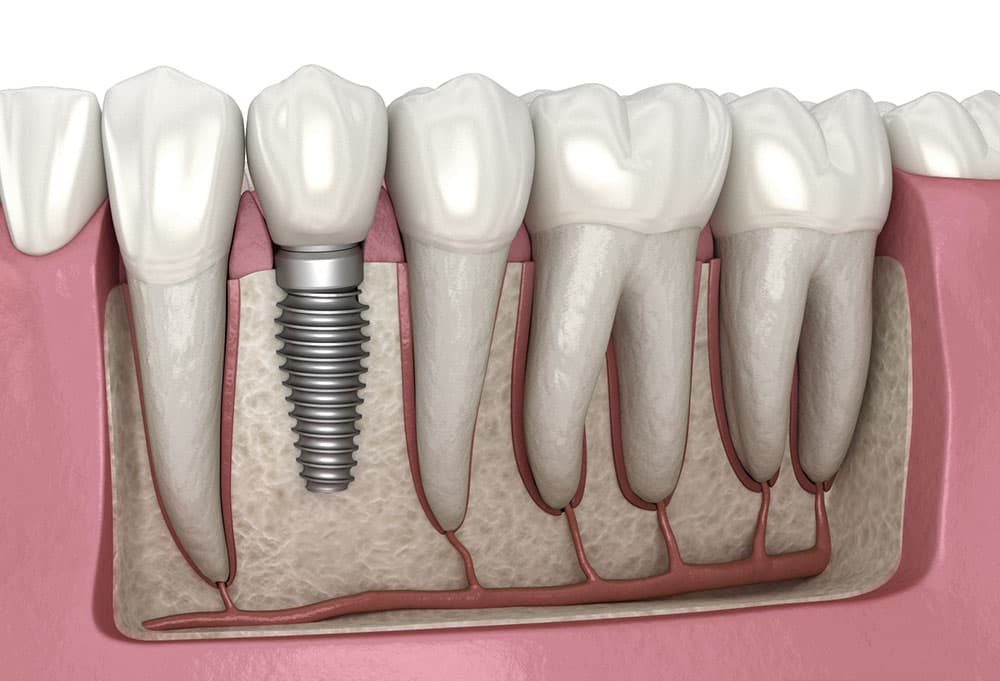

Title: Specialiste SSO en parodontologie. Treats gum diseases (gingivitis, periodontitis), bone loss around teeth, and the placement and maintenance of dental implants.

When to see one: bleeding gums that do not improve with brushing, receding gums, loose teeth in adults, implant planning, peri-implantitis.

Title: Specialiste SSO en medecine dentaire reconstructive. This is the Swiss equivalent of prosthodontics. Covers crowns, bridges, inlays, onlays, full-mouth rehabilitations and implant-supported restorations.

When to see one: full-mouth rehabilitation, multiple crowns or bridges, implant prosthetics, aesthetic cases with veneers, severe tooth wear.

Unlike the US or UK, Switzerland does not recognise endodontics (root canals) or implantology as separate SSO specialties. Endodontics is covered by the reconstructive dentistry title, and implantology is shared between oral surgery, periodontology and reconstructive dentistry. However, many clinics advertise dentists with post-graduate master’s degrees in these areas (e.g. MSc in Endodontology, MSc in Implantology), which is a good secondary quality marker.

| Dental implant (single, incl. crown) | CHF 2,500 | CHF 3,800 | CHF 5,500 |

- What implant systems do you use? (Good answers: Straumann, Nobel Biocare, Astra Tech, Dentsply. Unknown brands are a red flag.)